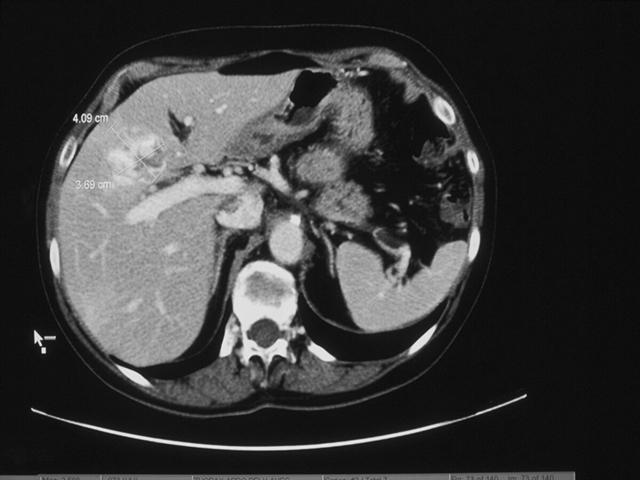

瘦弱的小夏脸色蜡黄,医生原本以为这个年轻小伙是低血糖之类的小毛病,抽血化验后,却发现肝功各项指标都是异常的,进一步检查确认,小夏已经是肝癌晚期了。